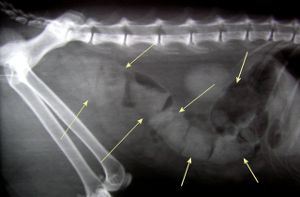

House call veterinarians can do most of the same things that are done in a clinic setting. Some of these veterinarians have mobile clinics set up in vans or modified recreational vehicles, which can be equipped with surgery suites and x-ray machines. Other house call veterinarians work out of cars and do all appointments in the home, referring pets needing surgery or hospitalization to local brick and mortar clinics.